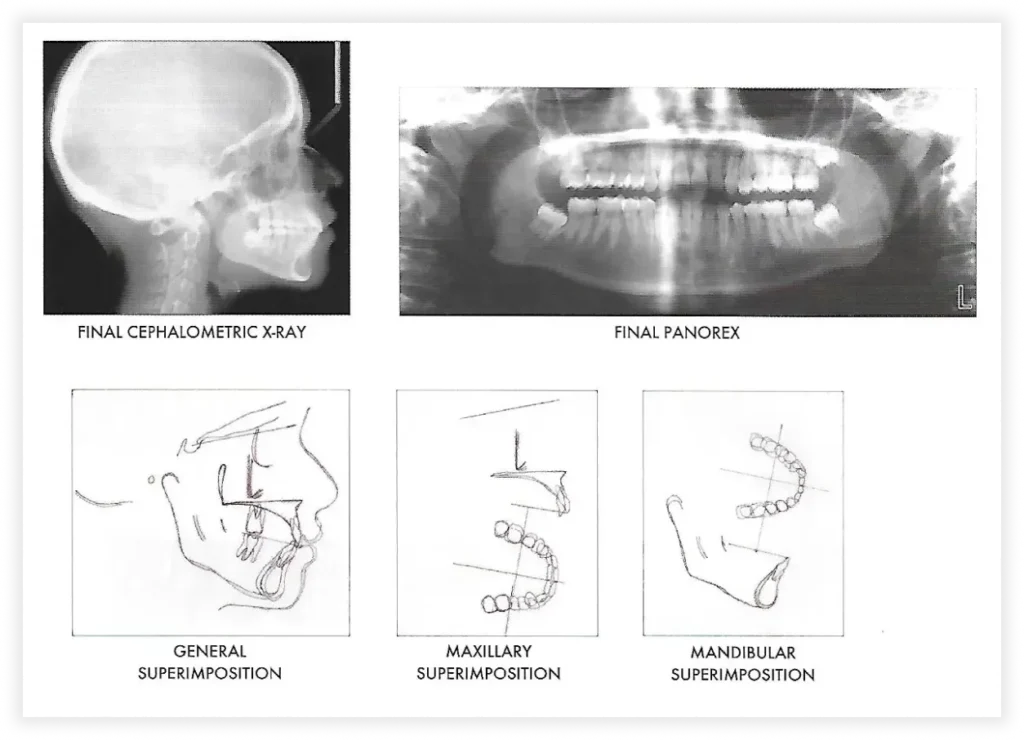

Final Photos